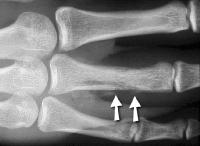

Radiographs show evidence of osteomyelitis with bone erosion and subperiosteal bone formation (arrows).